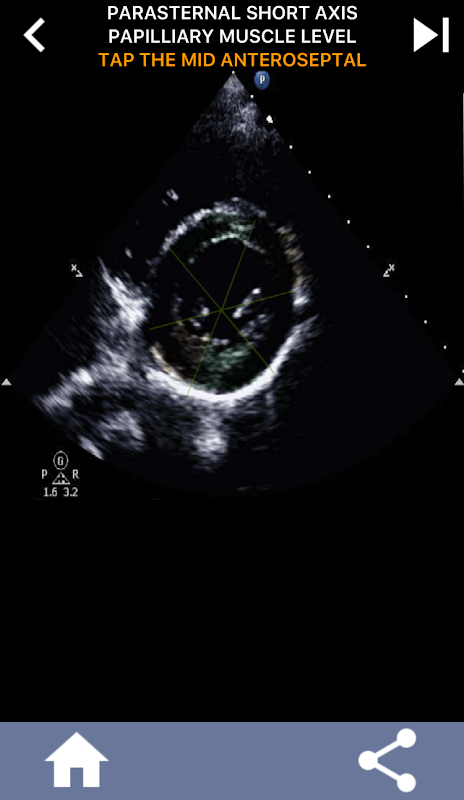

এই বোঝাপড়াটি বিশেষভাবে গুরুত্বপূর্ণ হয়ে ওঠে যখন কার্ডিওলজিস্ট কোনও সমস্যার সঠিক অবস্থান নির্ণয় করার চেষ্টা করেন বা যখন কল করা চিকিত্সক একটি নির্দিষ্ট অঞ্চলের মধ্যে একটি সমস্যা সনাক্ত করেন, সোনোগ্রাফারকে সঠিকভাবে সংশ্লিষ্ট বিভাগ যেমন মধ্য-নিকৃষ্ট প্রাচীর প্রদর্শন করতে প্ররোচিত করে। এইভাবে, AHA হার্ট সেগমেন্টগুলির একটি বিস্তৃত উপলব্ধি থাকা অপরিহার্য দক্ষতা সেট।

এই অ্যাপটি প্রকৃত ইকো ইমেজ ব্যবহার করে আপনার জ্ঞান পরীক্ষা করবে, যা আমি প্রায়শই সেরা শিক্ষার পদ্ধতি বলে মনে করি।